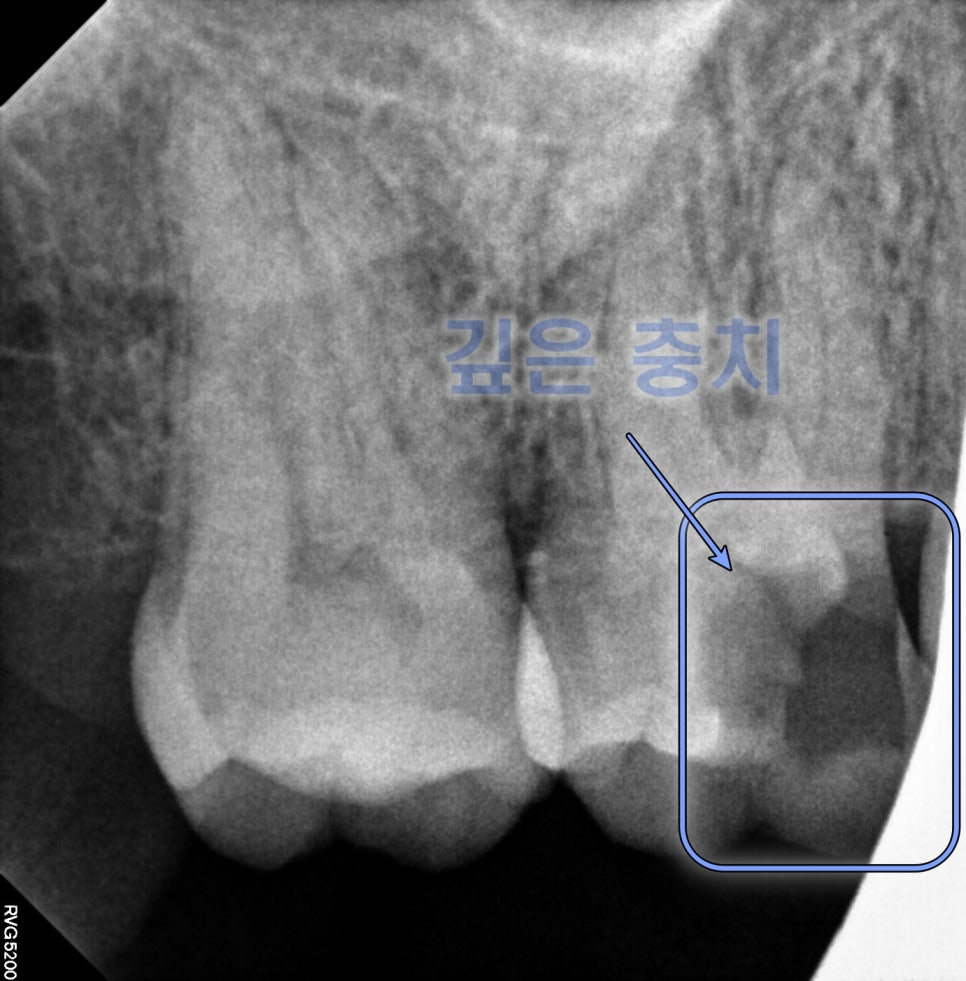

또 엑스레이를 보면

깊숙한 우식증을

볼 수 있는데요.

치근까지 우식이 진행되어서

살리기가 어렵다고 판단이 되는데요.

그래서 이제는 기능을 못하는 치아는

발치 후 임플란트 치료를 진행해야 됩니다.